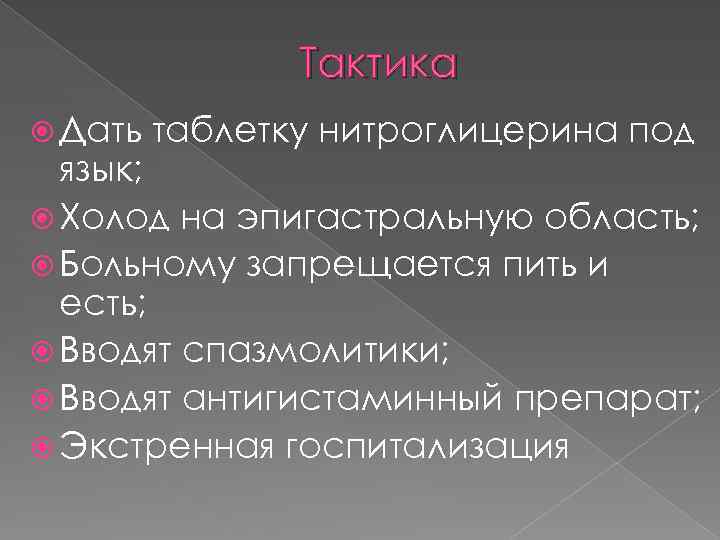

Тактика Дать таблетку нитроглицерина под язык; Холод на эпигастральную область; Больному запрещается пить и есть; Вводят спазмолитики; Вводят антигистаминный препарат; Экстренная госпитализация

Тактика Дать таблетку нитроглицерина под язык; Холод на эпигастральную область; Больному запрещается пить и есть; Вводят спазмолитики; Вводят антигистаминный препарат; Экстренная госпитализация